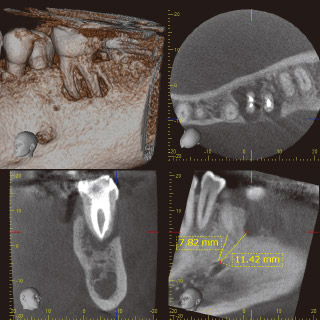

ただ、どのような症例もCBCTで撮影すれば治療の成功率が劇的に上がるというものではありません。撮影を実施するかどうかは、ヨーロッパのガイドラインに「患者に被曝させることよりも撮影する利益が必ずうわまっていて、なおかつ最小の被曝量で撮影を行う」とあるように、医療人としての倫理観が問われます。当院では、おもに2つのケースに活用しています。一つは、外科手術を行う際の安全面に考慮した場合。下顎大臼歯部に歯根端切除手術を行う際、術野からオトガイ神経までの距離の測定などに役立てています。もう一つはご紹介をうけた患者さんの治療計画を立てる際、診断が複雑で三次元的な解析が必要な場合や、患歯の特定が困難な場合に用いています。

症例1-3 根尖より3mmの位置での近心根の頰側から舌側までの厚みを測定。 -

症例1-4 オトガイ孔から近心根ならびに5までの距離の測定。 -